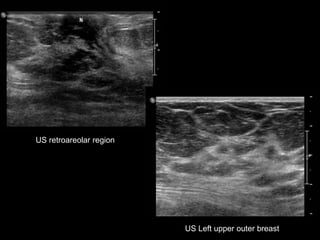

US retroareolar region

US Left upper outer breast

US retroareolar region US Left upper outer breast